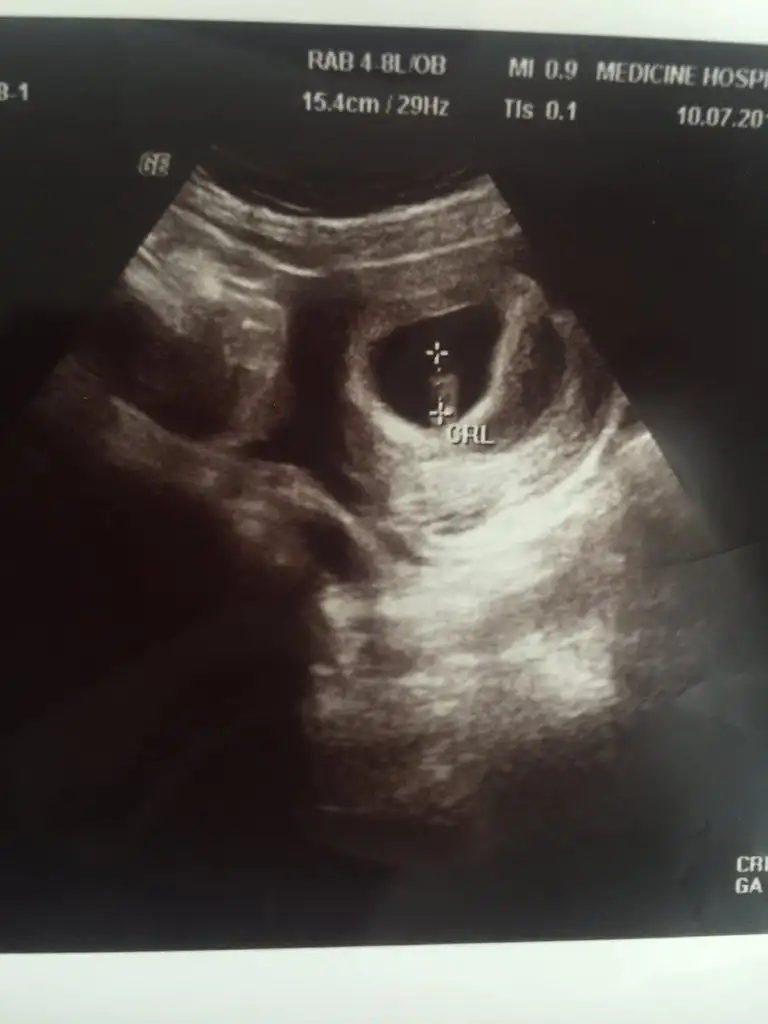

Kizlar 8+0 usg fotografimiz tahminlerinizi bekliyorum karından bakıldı

Ama bi kac tane ayni gunden usg var biri daha saga biri daha sola yakin ne olcak simdi :)

• 20190710_202259.webp

20,1 KB · Görüntüleme: 344